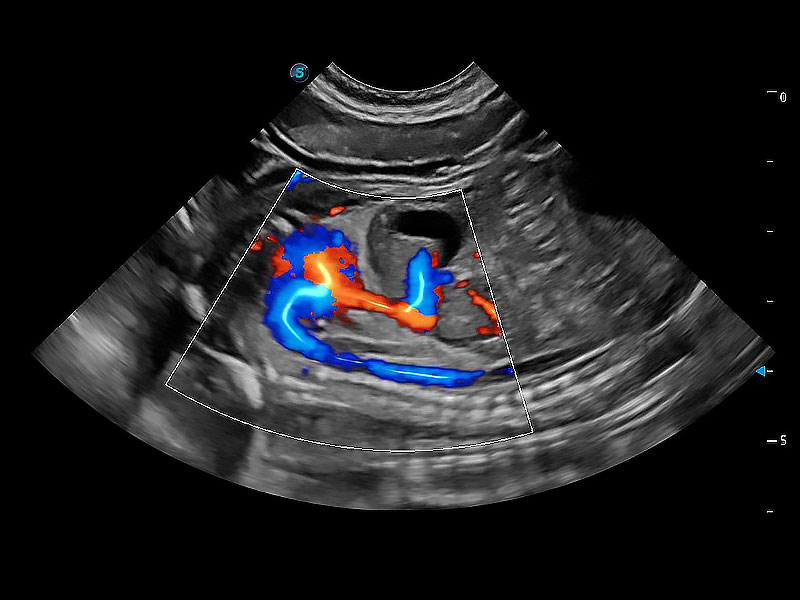

(犬)二腔心血流

(犬)胎儿主动脉弓立体血流

• Bright Flow 立体血流成像

在传统二维血流成像的基础上,呈现血流的立体感,具有动感的生命力之美。即便是微小的血管也能轻松应对,提高了血流的视觉敏感性。